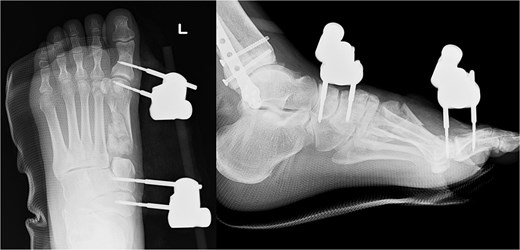

The external fixator was removed 4 weeks after the first surgery. Full weight-bearing was allowed 6 weeks after the operation. The plate was removed after confirming bone union. The patient was able to return to agricultural work 6 months postoperatively, and the American Orthopedic Foot and Ankle Society score 1 year post-surgery was 84. The follow-up radiography image taken at this stage is shown in Fig. 4.